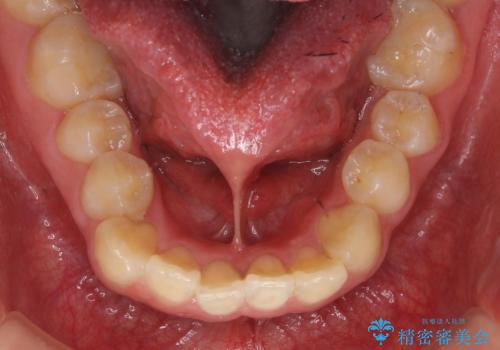

舌が持ち上がらない 舌小帯切除

舌を持ち上げた時に、ハート型になるのが適応症です。